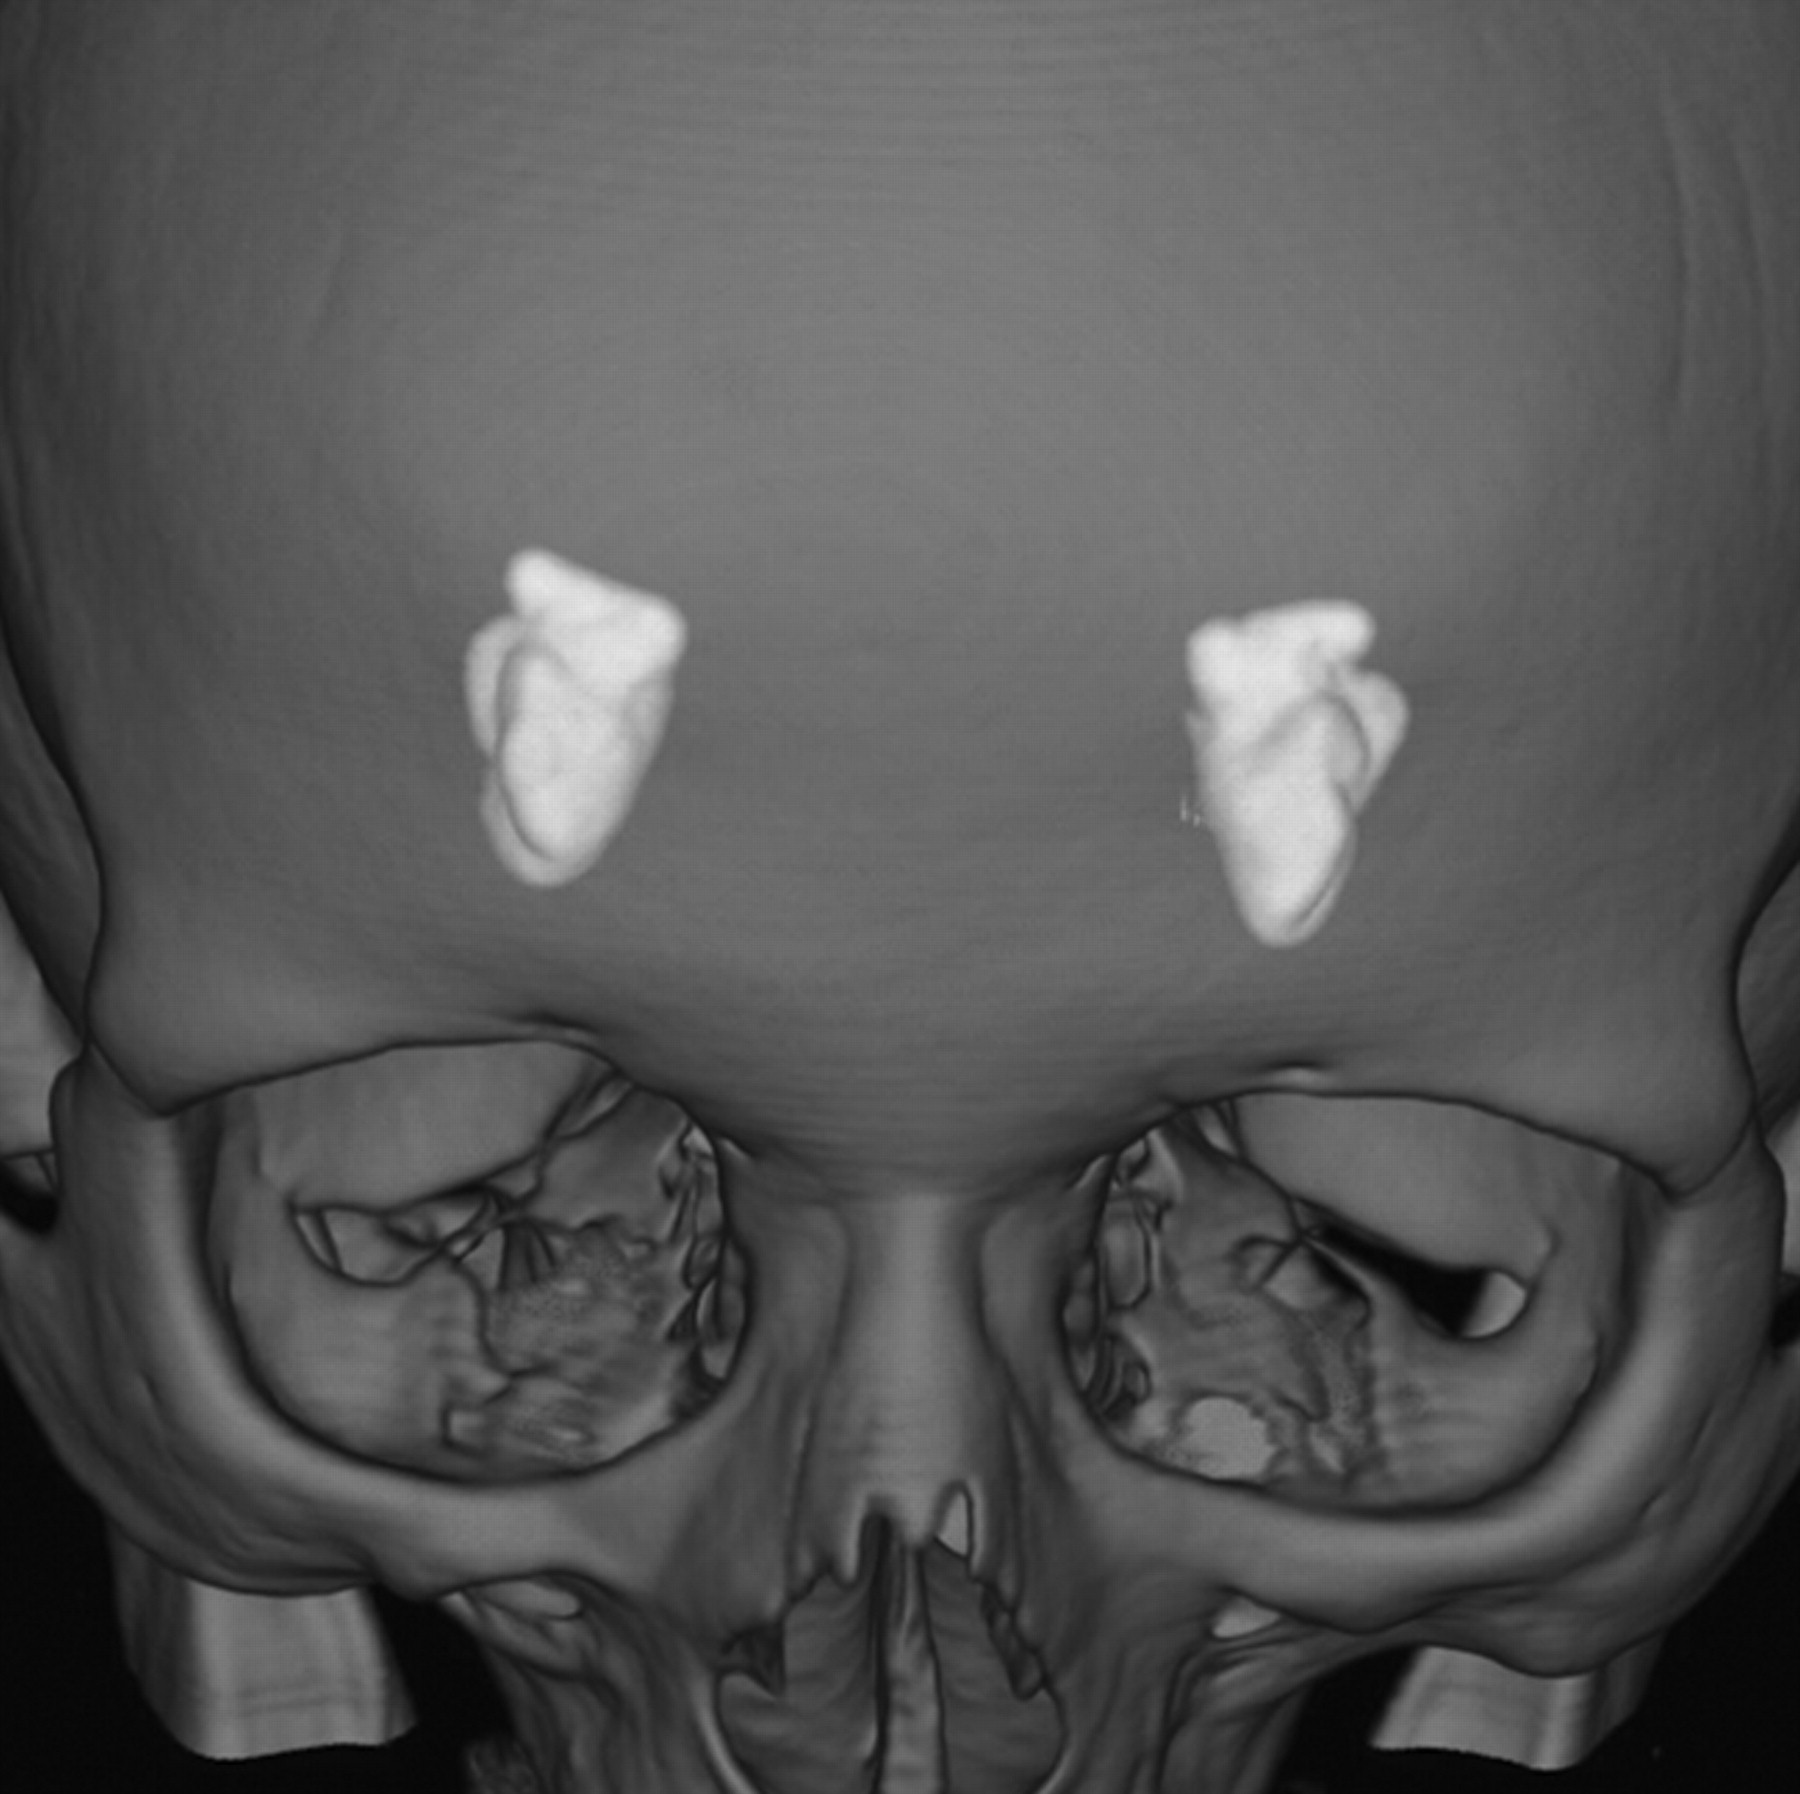

A 58-year-old female patient presented with a long history of throaty voice and very thin fragile hair, requiring the use of a wig for the past 20 years. She also had a history of bilateral submandibular gland enlargement and verrucous lesions throughout the joints, mainly in the groin and elbows. She complained of frequent and easy loss of temper, with a generalized disgust affect, possibly reflecting a degree of depression. There was no history of any seizures or focal neurologic deficits. On imaging, she had symmetric temporal lobe calcifications bilaterally. CT-based 3D-volume rendering demonstrated calcified lesions in the usual bilateral amygdaloid and uncal topography (Fig 4).

3D-volume rendering reformation from a volume CT acquisition shows, in perspective, the 2 “almond-shaped” symmetrically and mesially located calcifications in patient 2.